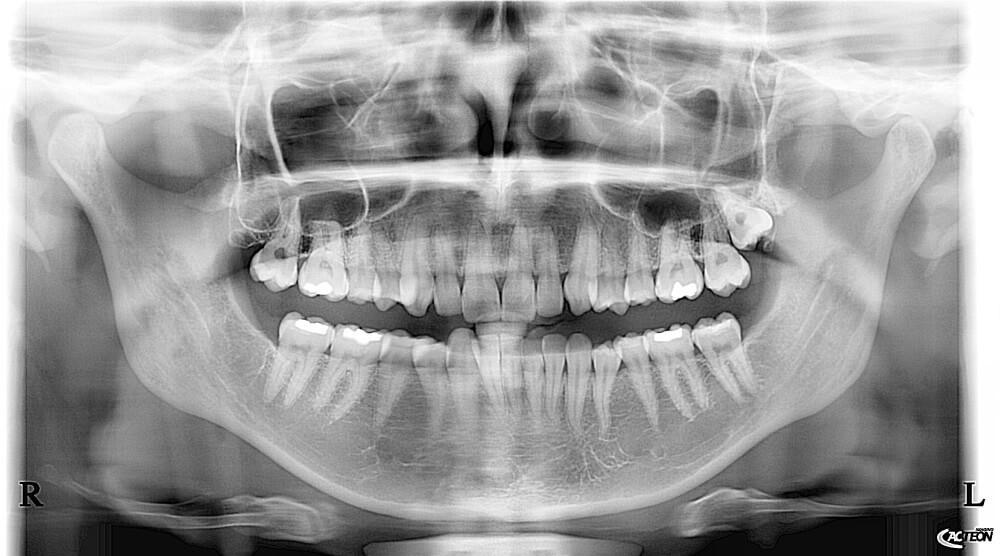

Tomografy CBCT są kluczowym elementem diagnostyki we współczesnej stomatologii. Uzyskiwane za ich pomocą zdjęcia panoramiczne, cefalometryczne i tomograficzne pozwalają lekarzom na dokładne planowanie zabiegów i szczegółową kontrolę rekonwalescencyjną przy minimalnej dawce promieniowania.

Tomografy CBCT służą do kompleksowej diagnostyki stomatologicznej. Umożliwiają zdobycie informacji, niezbędnych do wykrywania i oceny zmian w jamie ustnej. Odbywa się to poprzez dokładne obrazowanie wszystkich tkanek miękkich i kostnych szczęki, żuchwy, twarzy, łuku zębowego oraz zatok za pomocą zdjęć panoramicznych, cefalometrycznych i tomograficznych.

Aparat CBCT stomatologiczny powinien mieć możliwość robienia zdjęć panoramicznych, cefalometrycznych w skali 1:1 oraz tomograficznych. Wykonywanie ich powinno być możliwe w zakresie wielu pól obrazowania. Taki aparat będzie maksymalnie funkcjonalny, nie wymagając od nas zakupu dodatkowych urządzeń. Dobry tomograf pozwoli także na precyzyjne zaplanowanie zabiegu implantacji – wytyczenie przebiegu kanału nerwu zębodołowego dolnego, analizę gęstości kości w różnych płaszczyznach, określenie optymalnej wielkości implantów, pomiar potrzebnego wolumenu materiału kościozastępczego i obrazowanie gęstości kości wokół implantu.